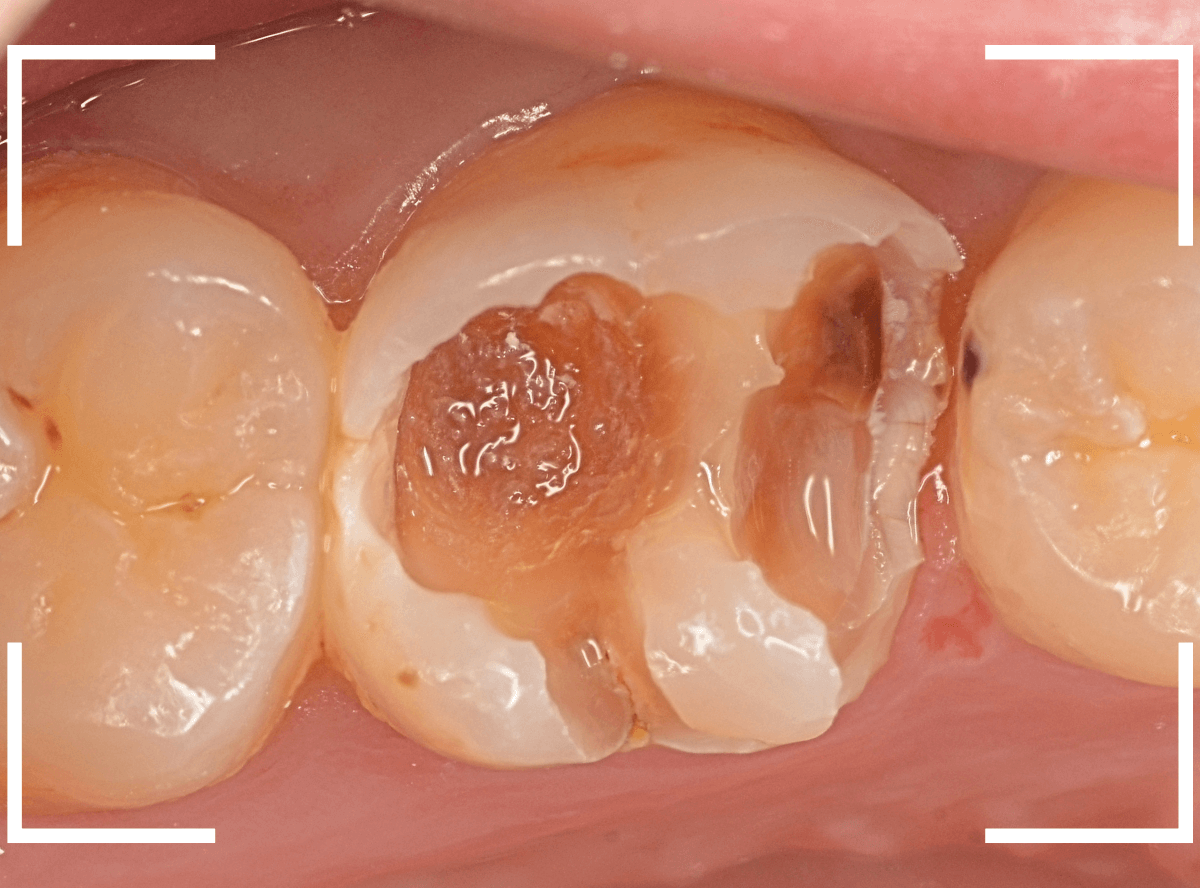

金属を外したところです。

写真では写ってしませんが、この奥に虫歯があります。

全ての虫歯を除去したところです。

抜歯した後ろのおやしらずは、元々虫歯の治療がしてありましたが、その際に抜歯しておいた方が良かったのではないかな、と思いました。